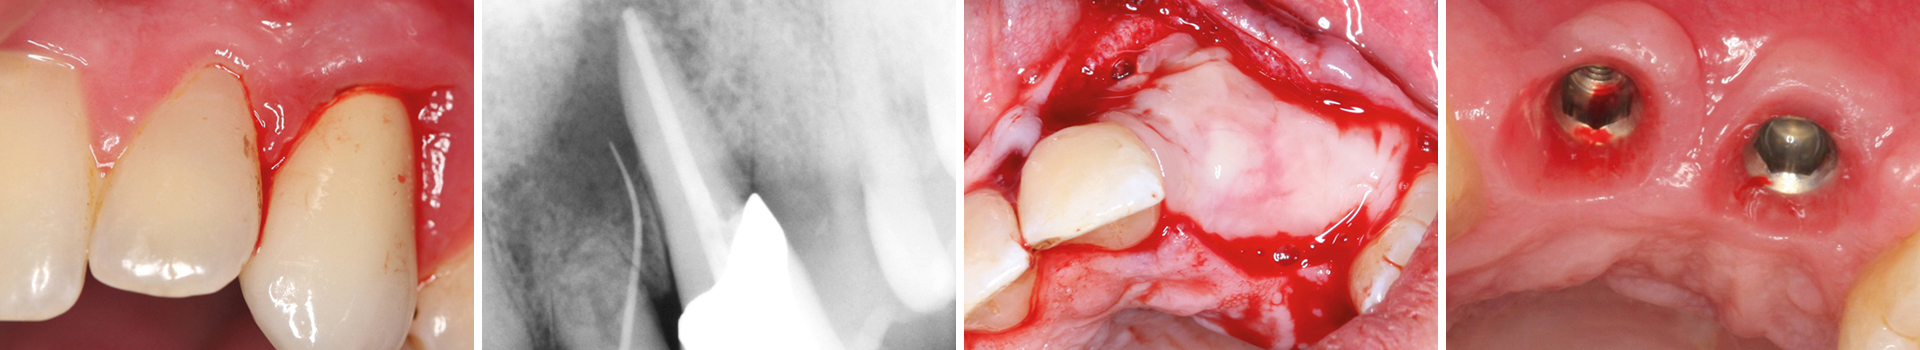

Abbildung 1

Klinische Ausgangssituation lateral, spontane Blutung.

Abbildung 2

Radiologische Ausgangssituation 22, 23.

Abbildung 3

Leere Alveole nach atraumatischer Extraktion.

Abbildung 4

Auffüllen des Defekts mit PRGF Endoret.

Abbildung 5

Provisorium.

Abbildung 22

Darstellung der Implantat-Kavitäten im neuen Knochen.

Abbildung 23

Darstellung des Weichgewebes 2 Monate nach OP.